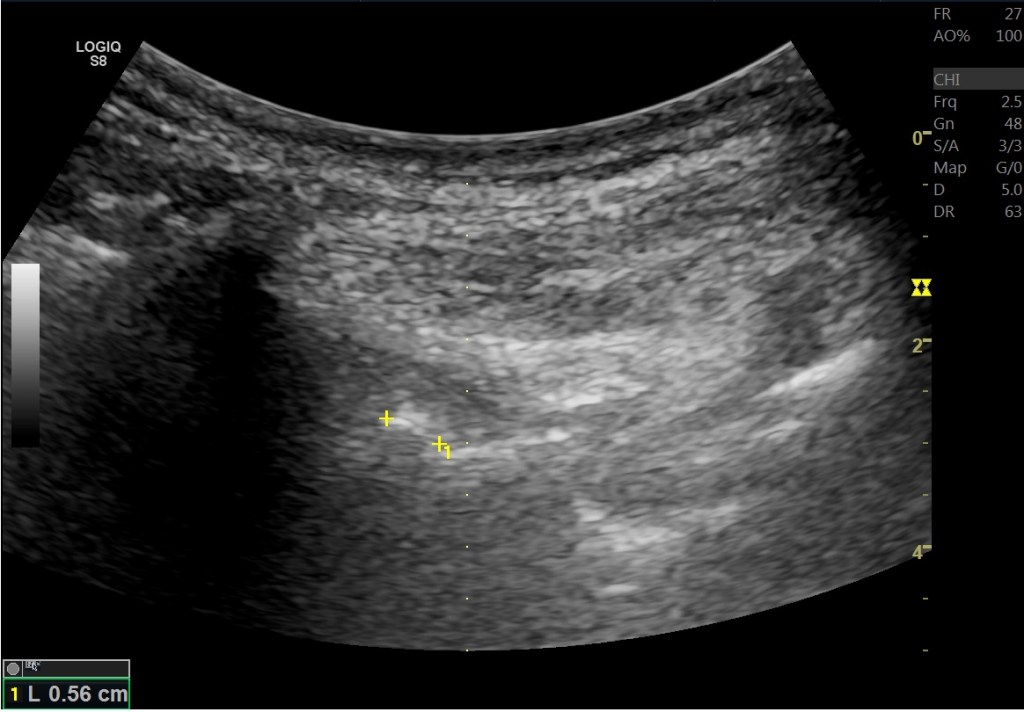

偶而可以看到髂腰韌帶疑似鈣化的位置。但有可能是之前受傷後的纖維化。

在超音波底下除了可以看到小面關節骨刺、韌帶撕裂、韌帶鈣化等等著病徵,甚至在肌肉層也會有一些變化。例如多裂肌的纖維化(Fatty fibrotic change)、豎脊肌的撕裂,這些都跟脊椎滑脫有關。